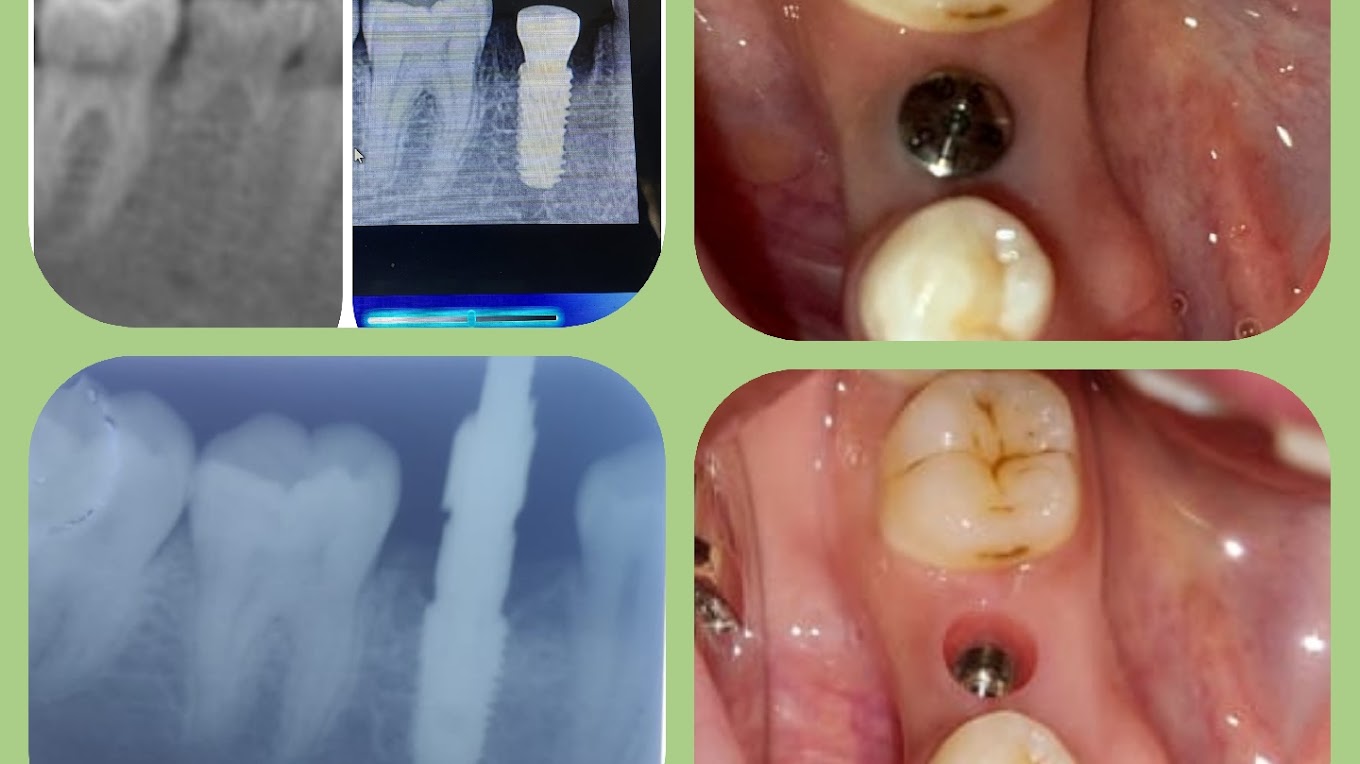

Restore your smile and confidence with state-of-the-art dental implants in Nagaram.

"I strongly recommend for dental implants. I was nervous about the procedure, but Dr. Bharath and the team made me feel completely at ease and understood my requirements. The process was smooth, and the result is life-changing—I can finally smile and eat with total confidence again. If you’re on the fence about getting implants, this is the place to go!"

I had a wonderful experience getting my dental implant done here.

Dr. Bharat Garu and Dr. Sathya Garu were both very kind, patient, and professional. They clearly explained each step of the procedure, even showing me a video for better understanding. The treatment was painless, well-organised, and done with great care in a sterile environment.

At Dr Bharat’s I had my implants done- these were done using the latest materials and most of all expertise. Dr Bharat treated me with kindness and I appreciated this. He explained in detail the procedure along with outcome. I have had treatment done in the US but found Dr Bharat’s clinic better in terms of service provided. I even had my American son-in-law have his wisdom teeth extraction done. He was more than satisfied.